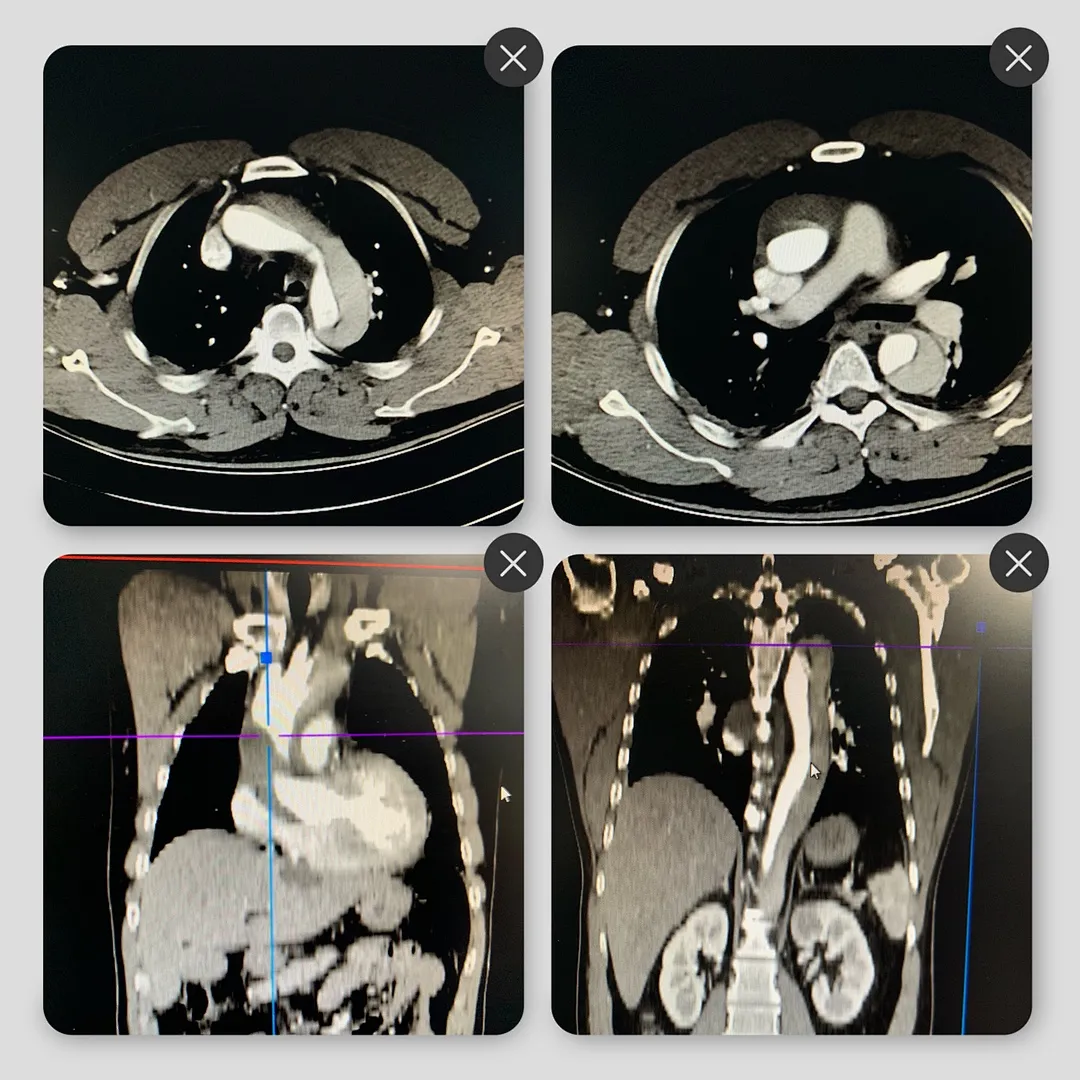

8月24日,心脏大血管外科顺利完成第4例主动脉夹层(A型)主动脉瓣成形术+升主动脉置换术+主动脉全弓置换术+象鼻子支架植入术,为凶险型主动脉夹层患者赢得生机。